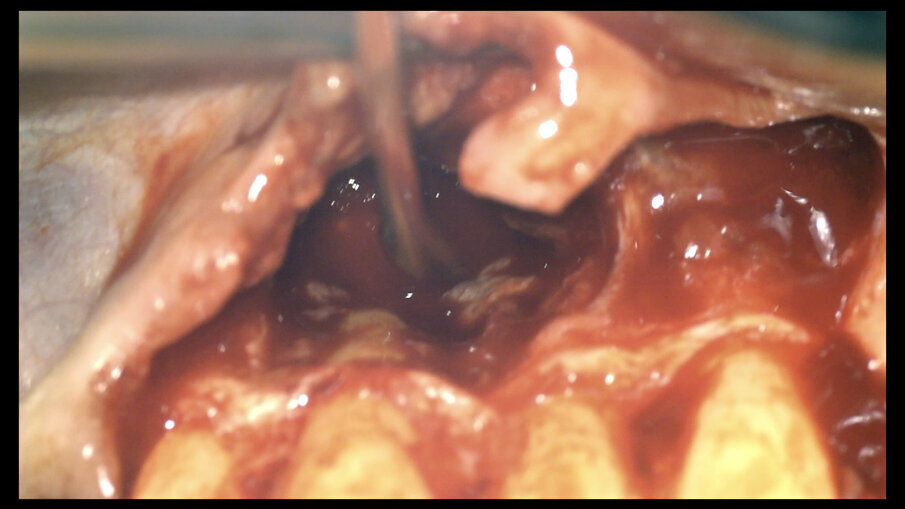

Slika 3: Tehnika nulte apikotomije izvedena na oba centralna sekutića

U jednoj sesiji urađena je terapija kanala korena oba centralna sekutića, podignut je režanj, cista je bila pažljivo uklonjena i površinski tretman oba korena je obavljen pažljivo (slika 3). Tokom postupka je neophodno da područje rada bude dobro hidrirano da bi se ćelije zadržale žive. Urađeno je čvrsto i uredno ušivanje, stavljen je tvrdi držač (ritejner) i proveren zagriz. Tvrdi držač je zamenjen posle šest nedelja mekim. Pacijentkinji su prepisani antibiotici sedam dana, ibuprofen nekoliko dana i bezalkoholna vodica za ispiranje usta s kojim je trebala da započne sedam dana nakon operacije.